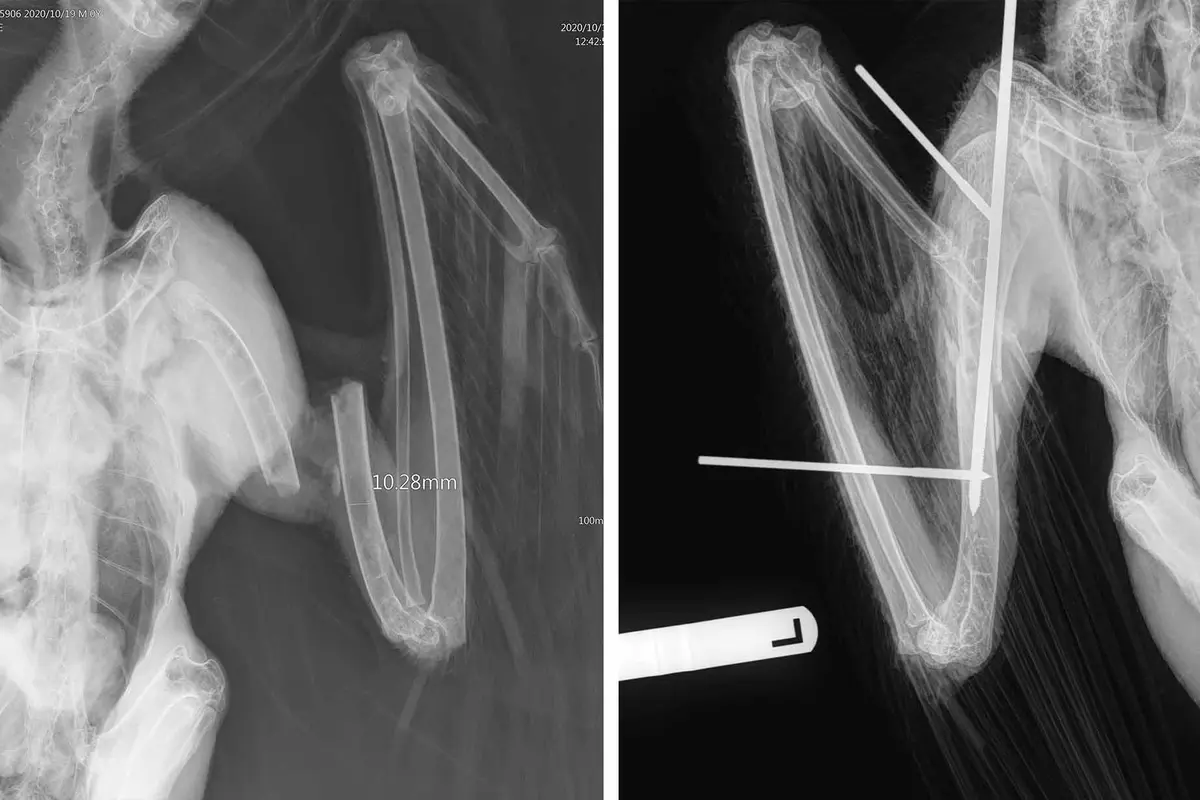

S úplně přetrženou pažní kostí, která jí prorazila křídlo, nemohla orlice létat. Redford a jeho asistenti věděli, že si musí pospíšit, má-li se jí vrátit schopnost létat.

Aby zachránili křídlo, museli chirurgicky vložit titanovou tyč podélně do dutého středu kosti a napříč k ní umístit několik menších šroubů.